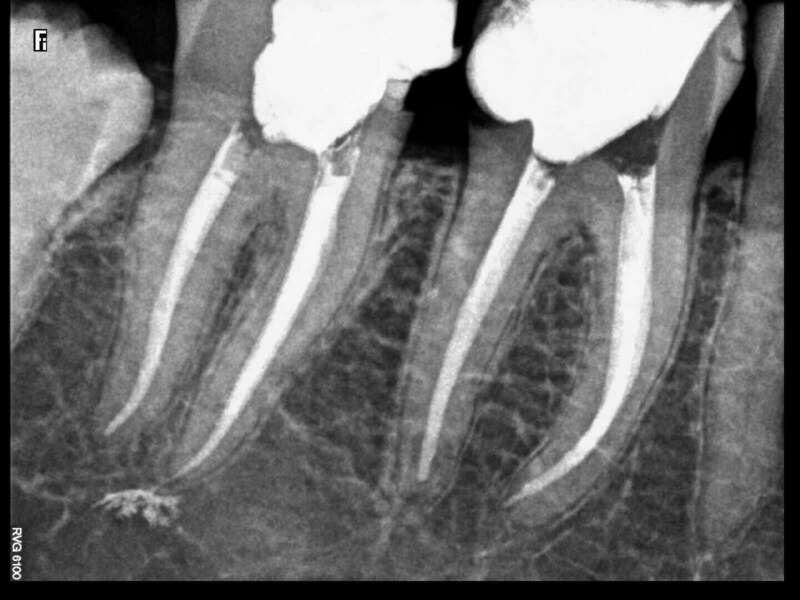

Cas du patient 4

Avant

Après